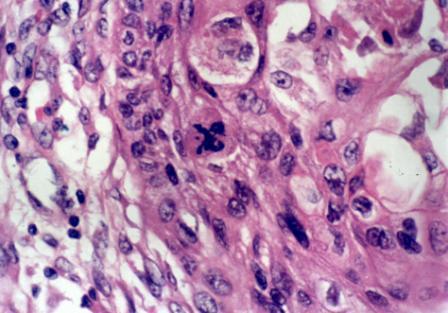

恶性肿瘤细胞(资料图)

恶性肿瘤生长迅速,侵犯周围组织,与周围组织无明显界线,质地较硬,无包膜,除体积较大外,还常向周围蔓延、扩散,有强大的破坏性和杀伤力。晚期常固定于某一器官组织上,出现坏死、溃疡及出血,并难于止血及愈合,手术不易切除,术后容易复发。而且癌细胞早期就可沿血管、淋巴管转移到其他部位。病理学检测,除了体积增大阻塞或压迫周围组织外,细胞完全失去正常生理功能,最后导致人的死亡。如:肺癌、鼻咽癌、食管癌、肾癌等。